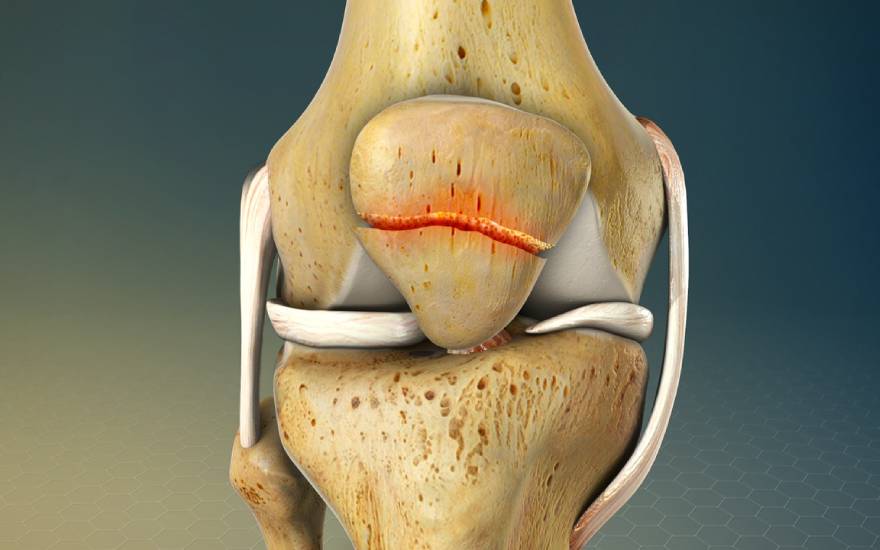

슬개골 골절은 지속적인 염증 반응으로 인해 관절낭 인대의 섬유화 및 석회화를 유발할 수 있습니다. 이러한 상태는 인대의 유연성을 저하시켜 무릎 관절의 강직(뻣뻣함)을 초래하고 운동 범위를 제한하게 됩니다.

3. 인대 섬유화 및 석회화 (Ligament Fibrosis and Calcification) 지속적인 염증 반응으로 인해 무릎 관절낭과 인대가 섬유화되거나 석회화될 수 있습니다. 이로 인해 인대의 탄력성이 저하되어 무릎 관절이 딱딱하게 굳고, 결과적으로 관절 가동 범위(ROM)가 현저히 감소하게 됩니다.

슬개골 골절은 지속적인 염증 반응으로 인해 관절낭 인대의 섬유화 및 석회화를 유발할 수 있습니다